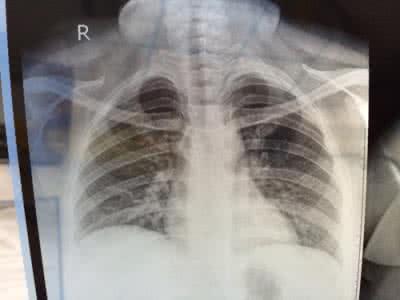

病人病情逐渐加重,或在暂时的改善后临床症状进一步加重,咳嗽,咳脓痰,并且出现肺部实变体征,X线发现肺部有片状和斑片状阴影。Reye综合征。